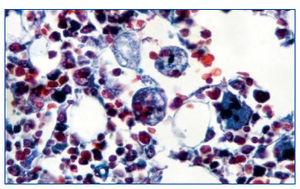

Figura 1. Tricrómico. Histiocitos con hematíes en su interior indicando su actividad hematófaga en la médula ósea.

Hombre de 53 años, sometido a trasplante renal que acude a urgencias por presentar cuadro febril con temperatura de 38,5 ºC de 24 horas de evolución con escalofríos, dolor abdominal leve difuso, astenia, anorexia y disminución subjetiva del volumen de diuresis. La exploración física fue normal y en las diferentes pruebas practicadas de urgencia no se encontró patología relevante: radiografías normales, analítica de sangre y orina normal, hemocultivo y urocultivo negativo, antígeno precoz CMV negativo (en este momento no se disponía de PCR de CMV en nuestro hospital). El cuadro progresó con un aumento del dolor abdominal, en la tomografía axial computarizada (TAC) se observó dilatación de asas de delgado de posible etiología isquémica o infecciosa. Ante los hallazgos y el empeoramiento clínico se realizó laparotomía exploratoria sin observarse anomalías. En el líquido peritoneal creció un estafilococo coagulasa negativo tratado con meropenem a dosis de 500 mg cada 12 horas. Tras la intervención presentó una mejoría clínica a pesar de la aparición de íleo paralítico posquirúrgico con resolución espontánea del mismo. A los pocos días aparecieron nuevos picos febriles junto con cuadro diarreico, inicialmente sin productos patológicos pero, posteriormente con melenas, asociado a deterioro neurológico, hepatoesplenomegalia, así como alteración función hepática, anemia y trombocitopenia. Se solicitaron nuevas pruebas en las que destacaron: antígeno precoz CMV positivo con PCR de CMV mayor a 100.000 copias/ml. Esoagogastroduodenoscopia: esofagitis infecciosa. Analítica: GOT/GPT 135/156 U/l; LDH 558 U/l; sodio 130 meq/l, fibrinógeno 133 mg/dl, hemoglobina 9,2 g/dl, y hematocrito del 26,8% y plaquetas de 48.000 µl con leucocitos normales (5.500 µl con fórmula normal), aumento muy importante de triglicéridos (738 mg/dl), deterioro progresivo de función renal (creatinina entorno a 4-5 mg/dl). Haptoglobina normal, test de Coombs negativo. Extensión sangre periférica: algún esquistocito con ausencia de reticulocitos. Punción de médula ósea: compatible con síndrome hemofagocítico (figura 1).

Ante dichos hallazgos, se diagnosticó al paciente de síndrome hemofagocítico reactivo a infección por CMV; se consultó con la unidad de enfermedades infecciosas y se inició terapia con la siguiente pauta: terapia anti-CMV con ganciclovir 50 mg/12 h y gammaglobulina inespecífica i.v. 30 g/48 h y para el síndrome hemofagocítico con bolos de metilprednisolona, manteniendo la ciclosporina que llevaba el paciente a dosis bajas (niveles en torno a 50 ng/ml). A pesar del tratamiento se produjo un deterioro del estado general y del estado neurológico y el paciente fue ingresado finalmente en la UCI por desaturación, donde falleció poco después por fallo multiorgánico, a los 12 días del ingreso. En la autopsia se observaron: infección por CMV diseminada, con afectación fundamental de tracto digestivo y pulmón (figura 2) y síndrome hemofagocítico reactivo (figura 1).